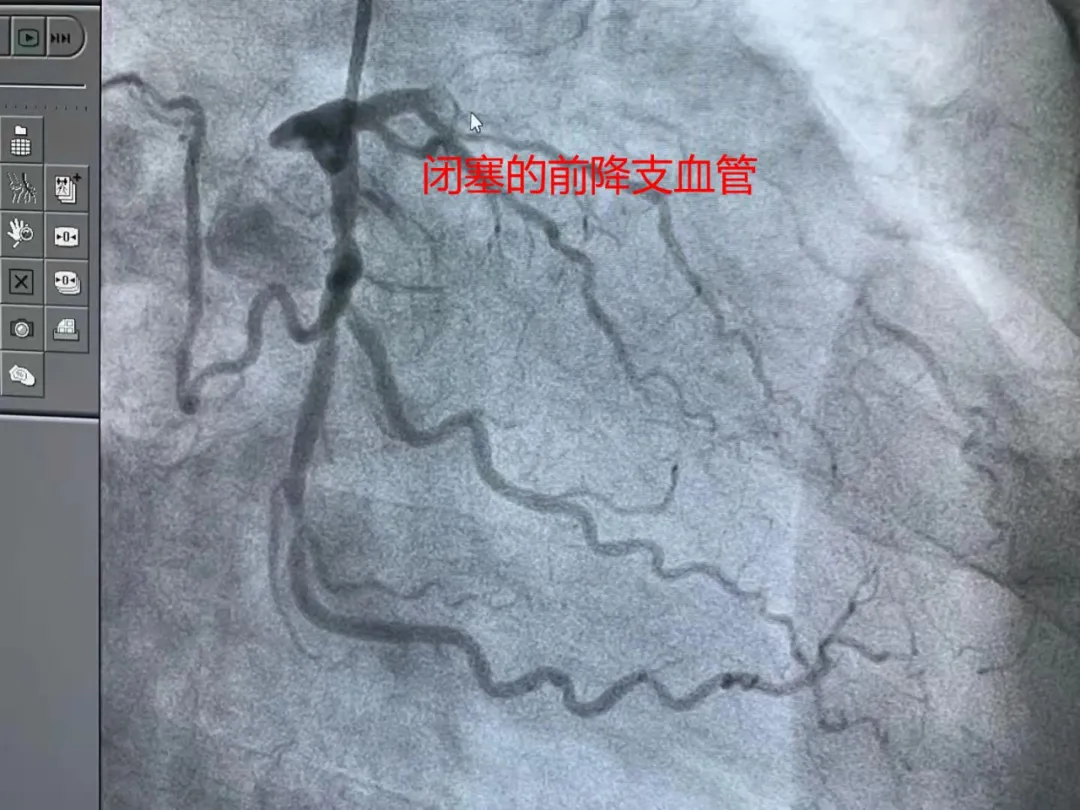

一個病人,10天前在某家醫院門診就診,症狀、檢查提示就是ACS,竟然沒急診住院。然後按處方吃藥不緩解,再住院,冠脈造影,結果就是下面圖中的情況。

萬幸沒有發生意外,也好在血管閉塞的時間短。如果時間久了,不僅病人的愈後生活質量很差,再開通的成功率也很低。

這是非常粗大的前降支血管開通,支架置入後的影像。